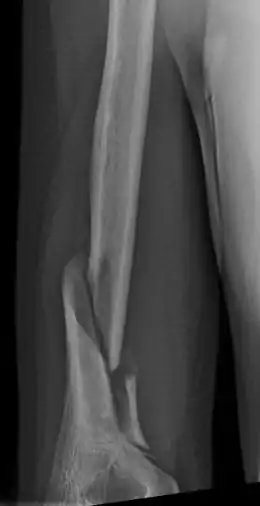

A Holstein–Lewis fracture is a fracture of the distal third of the humerus resulting in entrapment of the radial nerve.

| Holstein–Lewis fracture at 5 weeks post fracture | |